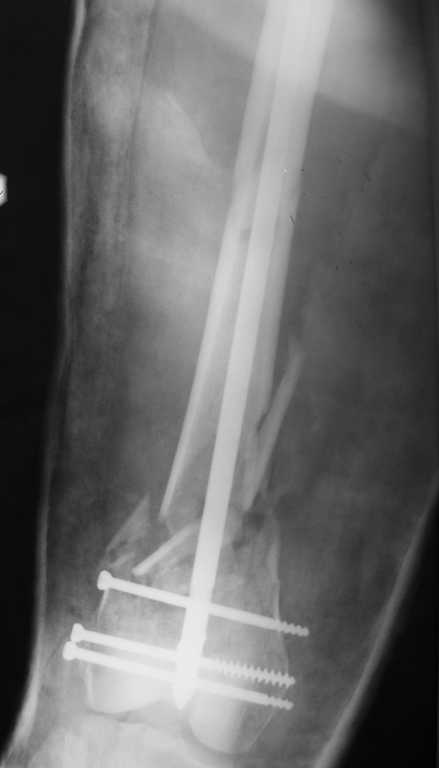

Результат операции блокирующего остеосинтеза многооскольчатого перелома бедра.

Применены винты собственной конструкции.(моделирование спогиозного винта) Хотелось бы

узнать рентгенологические результаты оперативного лечения

дистальных переломов бедра тибиальным стержнем.